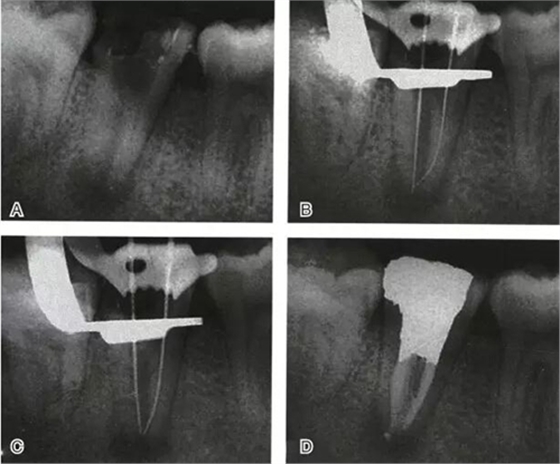

根管充填是C形根管治療成功與否的最重要因素。充填C形根管系統(tǒng)時(shí),近舌及遠(yuǎn)中根管可以進(jìn)行常規(guī)充填。關(guān)于狹區(qū)的充填,更適合以熱牙膠垂直加壓充填,這種方法可使牙膠到達(dá)根管系統(tǒng)的每一死角(圖4~7)。

圖4 Ⅰ型C形根管治療典型病例一,A:初始片,B:初尖銼片,C:主尖銼片,D:充填片